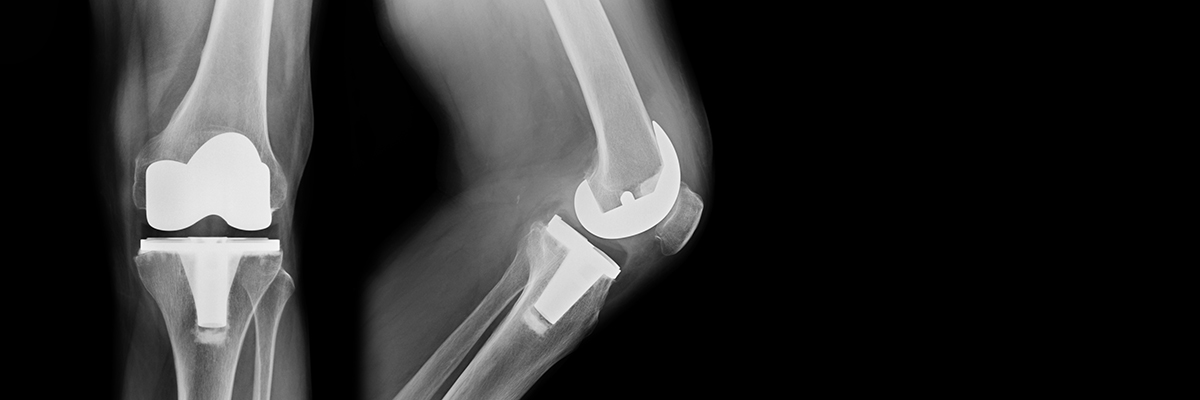

UAB Orthopaedic Surgery joint faculty and trainees deliver world-class, compassionate care in a community environment for patients with hip and knee arthritis.

Our team works to advance the science of hip and knee replacement through collaboration with experts in engineering, biosciences, and industry; and to educate other physicians in the care of patients with arthritis. We are comprised of health professionals dedicated to the operative and non-operative care of patients with arthritis of the hip and knee. Our surgeons are board certified and members of the American Association of Hip and Knee Surgeons.

The sole focus of our surgeons' practice is arthritis of the hip and knee. Our nurses, primary care physicians, OR staff, physical therapies, occupational therapist are integral to our efforts to return patients with hip and knee arthritis to the activities that they enjoy. Our patients are treated with the care, expertise, and attention to detail that we would want for our own family members. Learn more about options available to patients at UAB Medicine.